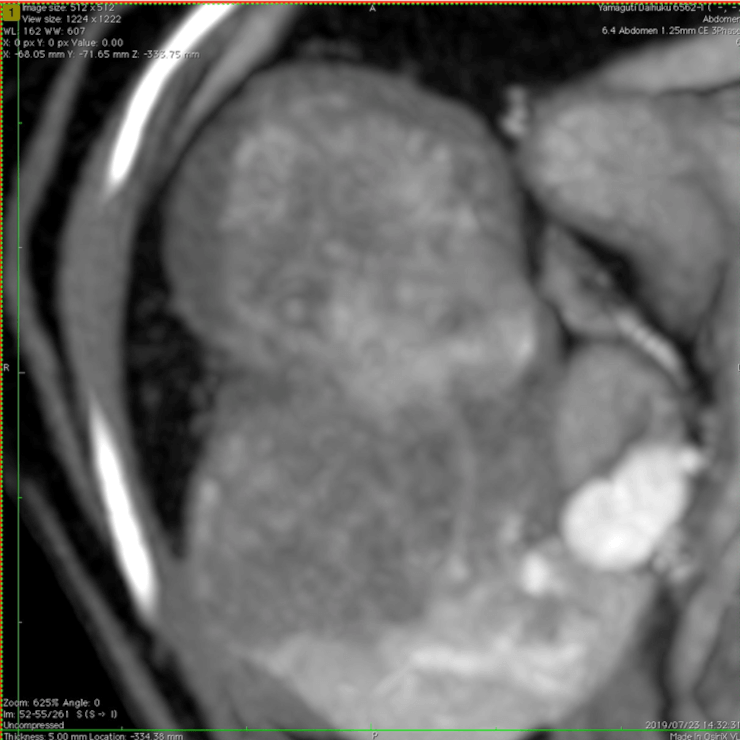

【実施症例】肝臓腫瘍に対する動注療法

柴犬、12歳、雄。

肝臓内側左葉に発生した巨大肝臓腫瘍。高齢で手術リスクが高いため、肝臓腫瘍に対して TACE(肝動注化学塞栓療法)を実施した。 実施から1ヵ月後のエコー検査で、腫瘍の若干の縮小と内部の壊死が認められた。

肝臓腫瘍の3D・CT画像